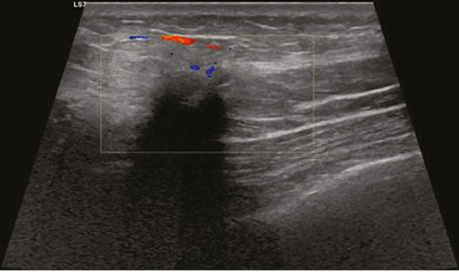

Виконано УЗД МЗ на діагностичному ультразвуковому приладі LOGIQ S7 Expert, GE Ultrasound Korea Ltd, Республіка Корея. У правій МЗ на 1 год визначалося гіпоехогенне гетерогенне новоутворення неправильної форми з нечіткими нерівними контурами, розміром 29×23×18 мм, з ознаками локусів інтранодулярного кровотоку при кольоровому доплерівському картуванні (КДК). Поруч візуалізувалися аналогічної структури: 3 новоутворення розміром 4; 5 та 8 мм, які не виявлялися на площинній мамографії через високу щільність паренхіми (рис. 2). У правій пахвовій ділянці лімфатичні вузли розміром до 23×17 мм, з гіпоехогенним, нерівномірно потовщеним кірковим шаром до 5 мм.

Рис. 2. УЗД правої МЗ. На 1 год — гіпоехогенне гетерогенне новоутворення неправильної форми з нечіткими нерівними контурами, з ознаками інтранодулярного кровотоку при КДК (a, b). Пухлинні новоутворення № 3, які не візуалізувалися на площинній мамографії (c, d)